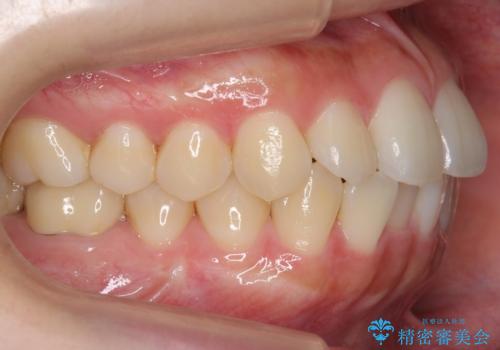

- 前歯のがたつきをきにされていました。

上下の前歯をやすりがけする処置(IPR)を行い、前歯の並びを出っ歯にしないようにしながら整えました。

症状が軽度であるためモニター採用になりました。